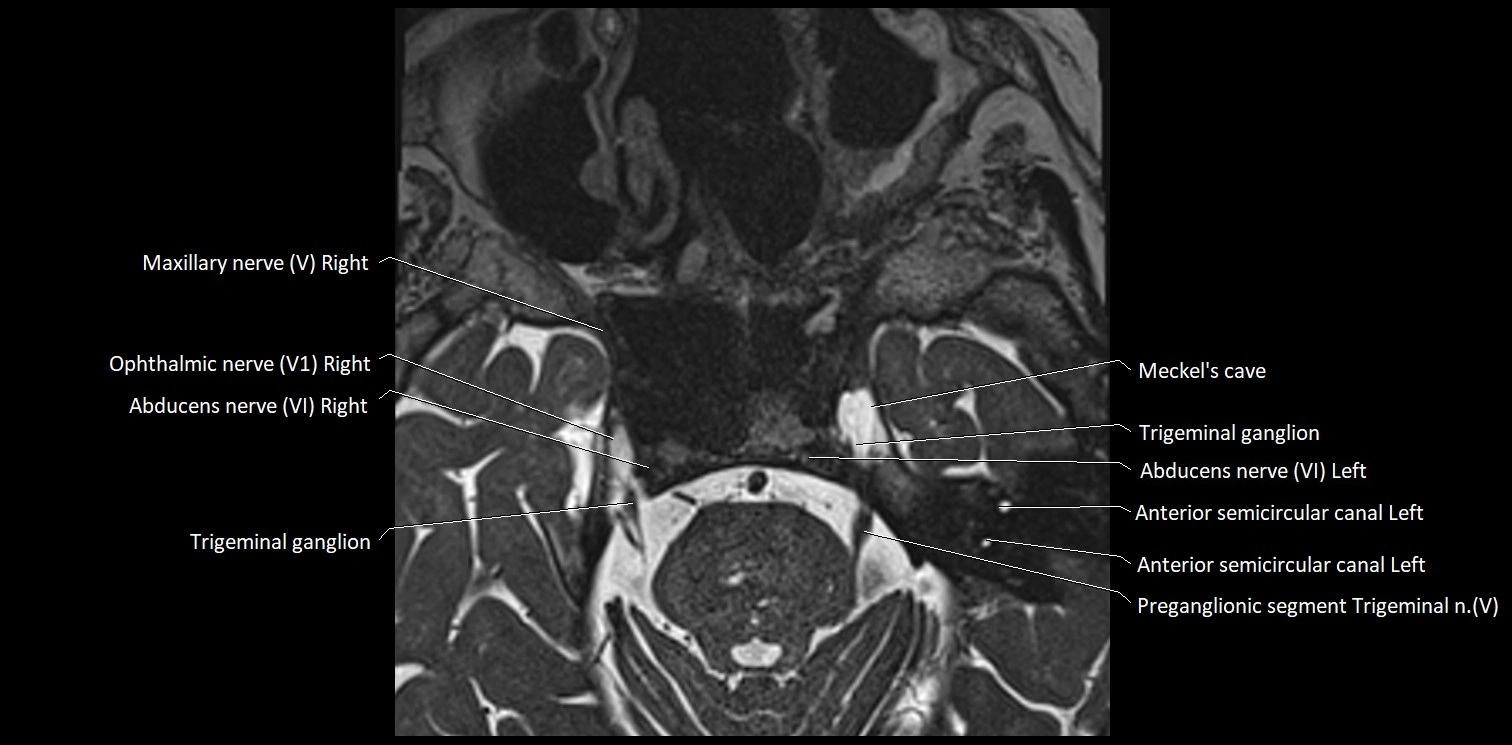

• The abducens nerve is a small, thin, linear structure

• Best visualized on high-resolution T2-weighted 3D MRI sequences (e.g., FIESTA or CISS)

• Seen as a hypointense (dark) line running from the brainstem at the pontomedullary junction, traversing the prepontine cistern, and entering Dorello’s canal under the petrosphenoidal ligament, then into the cavernous sinus, and finally the orbit

• May be challenging to visualize in standard MRI due to its small size

• Pathology may be inferred by absence, displacement, or enhancement of the nerve